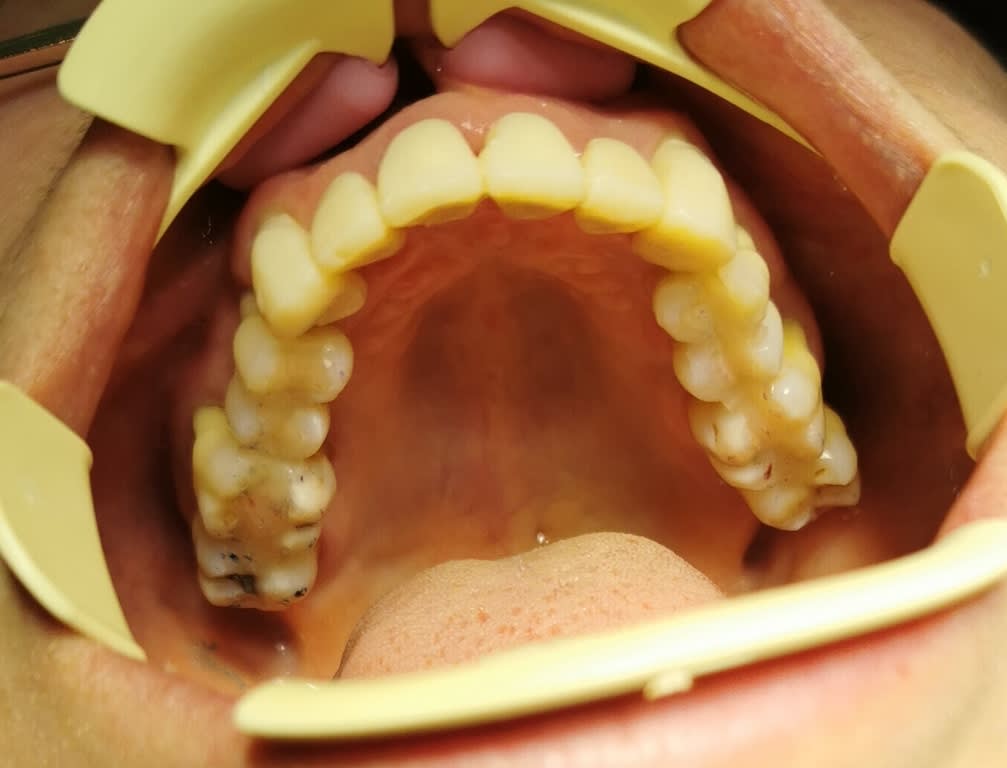

modèles de départ, photos avec le téléphone, désolé, mais ça donne une petite idée

--